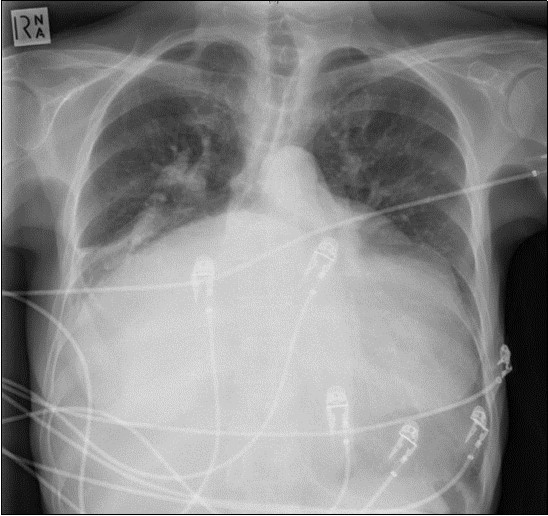

A 64-year-old woman was admitted to the Intensive Care Unit (ICU) after a medical emergency team (MET) call from the cardiology ward due to a reduced level of consciousness and respiratory distress. Past medical history included rheumatic fever as a child and chronic atrial fibrillation. She had been admitted to hospital 3 days previously with worsening shortness of breath. On observation she was drowsy but rousable to voice, with a respiratory rate of thirty breaths per minute. Examination revealed a raised jugular venous pressure, a pan-systolic murmur as well as a long mid-diastolic murmur, both loudest at the apex and radiating to the axilla, a soft first heart sound, a displaced tapping apex beat, and bi-basal medium-intensity inspiratory crepitations. Her electrocardiogram showed atrial fibrillation with a rapid ventricular response of 126 beats per minute. Her arterial blood gas demonstrated an acute on chronic respiratory acidosis with a pH 7.02, PaCO2 176 mmHg, and a HCO3- of 43 mmol/L. An antero-posterior (AP) chest x-ray on admission displayed cardiomegaly, splayed carina and hilar venous congestion, with a lateral film showing the left atrium occupying a significant part of the chest cavity (see Figure 1a, Figure 1b).

Figure 1a.Chest X-ray Antero-posterior view. Findings showing enlarged left atrium, splaying of the carina, hilar venous congestion

Chest X-ray Antero-posterior view. Findings showing enlarged left atrium, splaying of the carina, hilar venous congestion